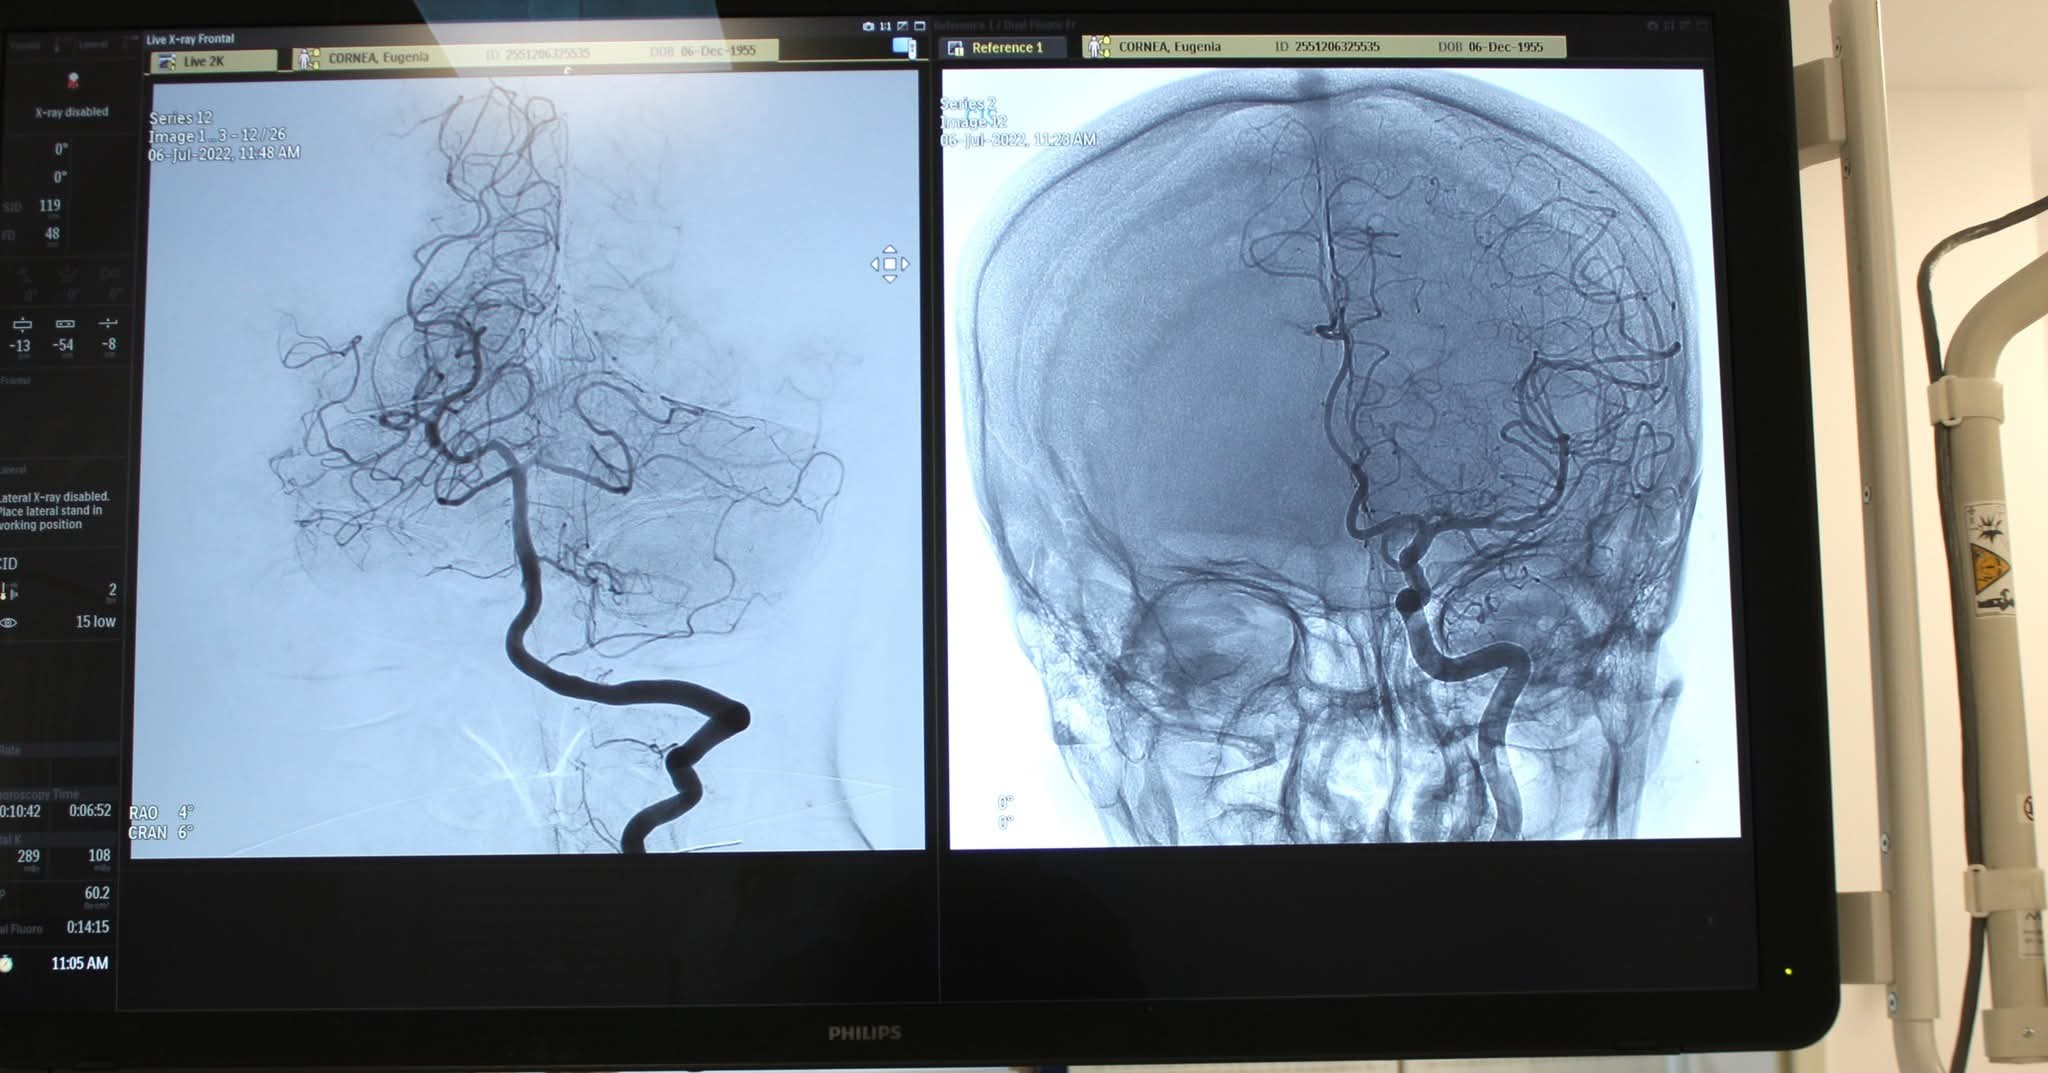

Consiliul Județean Sibiu investește aproape 25 de milioane de lei pentru tratamentul modern al accidentului vascular cerebral (AVC)